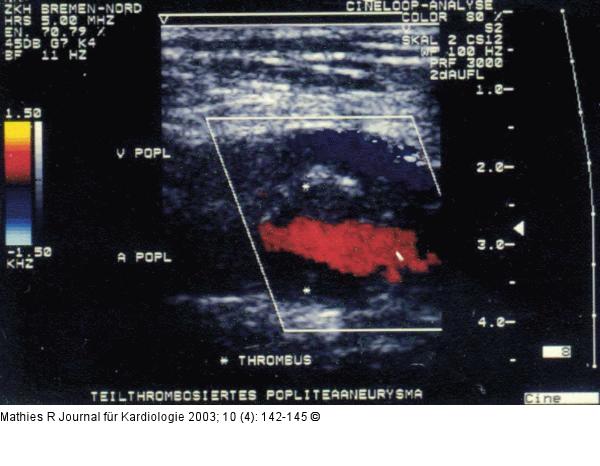

Abbildung 4: Popliteal Aneurysm CCD of popliteal aneurysm (angiography normal lumen) |

Abbildung 4: Popliteal Aneurysm

CCD of popliteal aneurysm (angiography normal lumen) |